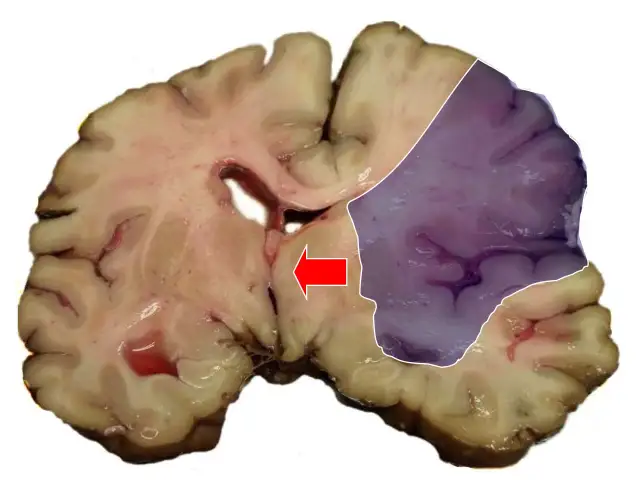

Udar mózgu to choroba, nie wypadek. Poznaj jej typy, przyczyny i objawy (test F.A.S.T.). Dowiedz się, jak szybko reagować i zapobiegać.

Udar mózgu: co to jest, objawy (FAST), pierwsza pomoc. Poznaj przyczyny, leczenie i skuteczną profilaktykę. Ratuj życie, działaj szybko!

Czy udar mózgu jest groźny? Poznaj statystyki, rodzaje i długofalowe skutki. Dowiedz się, jak minimalizować ryzyko i zwiększyć szanse na powrót do zdrowia.